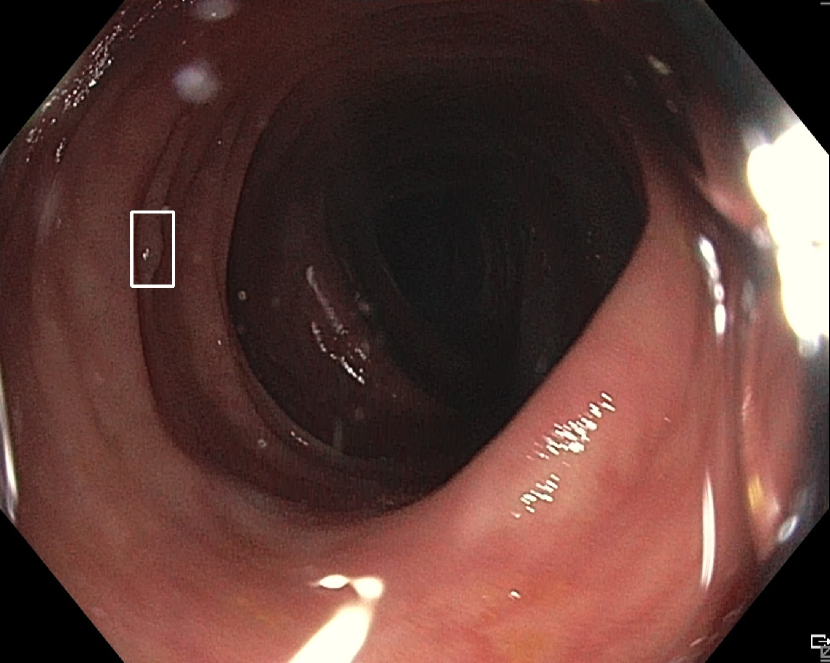

(h)

Figure 7: Sample images from the testing dataset, with results from the best performing model. White boxes are the ground truth annotations, blue ellipses are the model predictions. In the first row, examples of false negative polyps are shown: (7(a)) a small and distant polyp, (7(b)) a polyp partially covered by water/bubbles, (7(c)) a polyp framed in blue light, (7(d)) a large polyp near the image boundary and overexposed. In the second row, examples of false positive detections are shown: (7(e)) the model activates on a artifact due to stain and motion blur, (7(f)) the model activates on a solid residue, (7(g)) the model activates on an area of the colonic mucosa that is not well inflated, (7(h)) the model activates on a dark and distant area of the colonic mucosa whose shape is similar to a polyp.

Finally, in Figure 7, we display examples of false negatives and false positives from the test set, generated by the best performing model. To visually assess the performance on a whole video, we have uploaded a 60-minute colonoscopy video featuring 6 polyps, the longest in our test set, at https://figshare.com/s/fbb0834a21082984336c (with predictions marked in cyan and ground truth boxes in white). The image examples illustrate how the model struggles with small, occluded, or poorly imaged polyps, and generates false positives in areas that visually resemble polyps, often due to motion or suboptimal imaging. These observations persist throughout the entire video analysis, highlighting the importance of minimizing false positives throughout the entire procedure while maintaining high polyp recall.